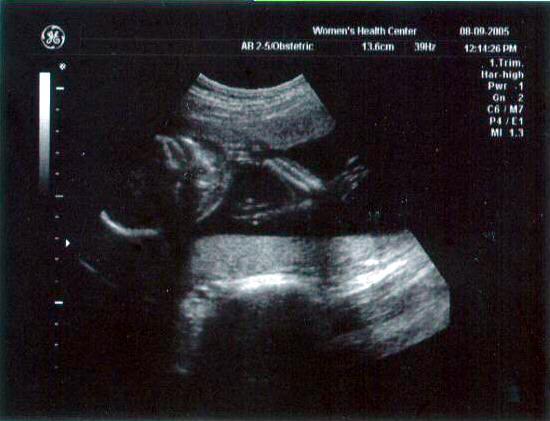

13 week ultrasound ~ The little one's getting bigger!